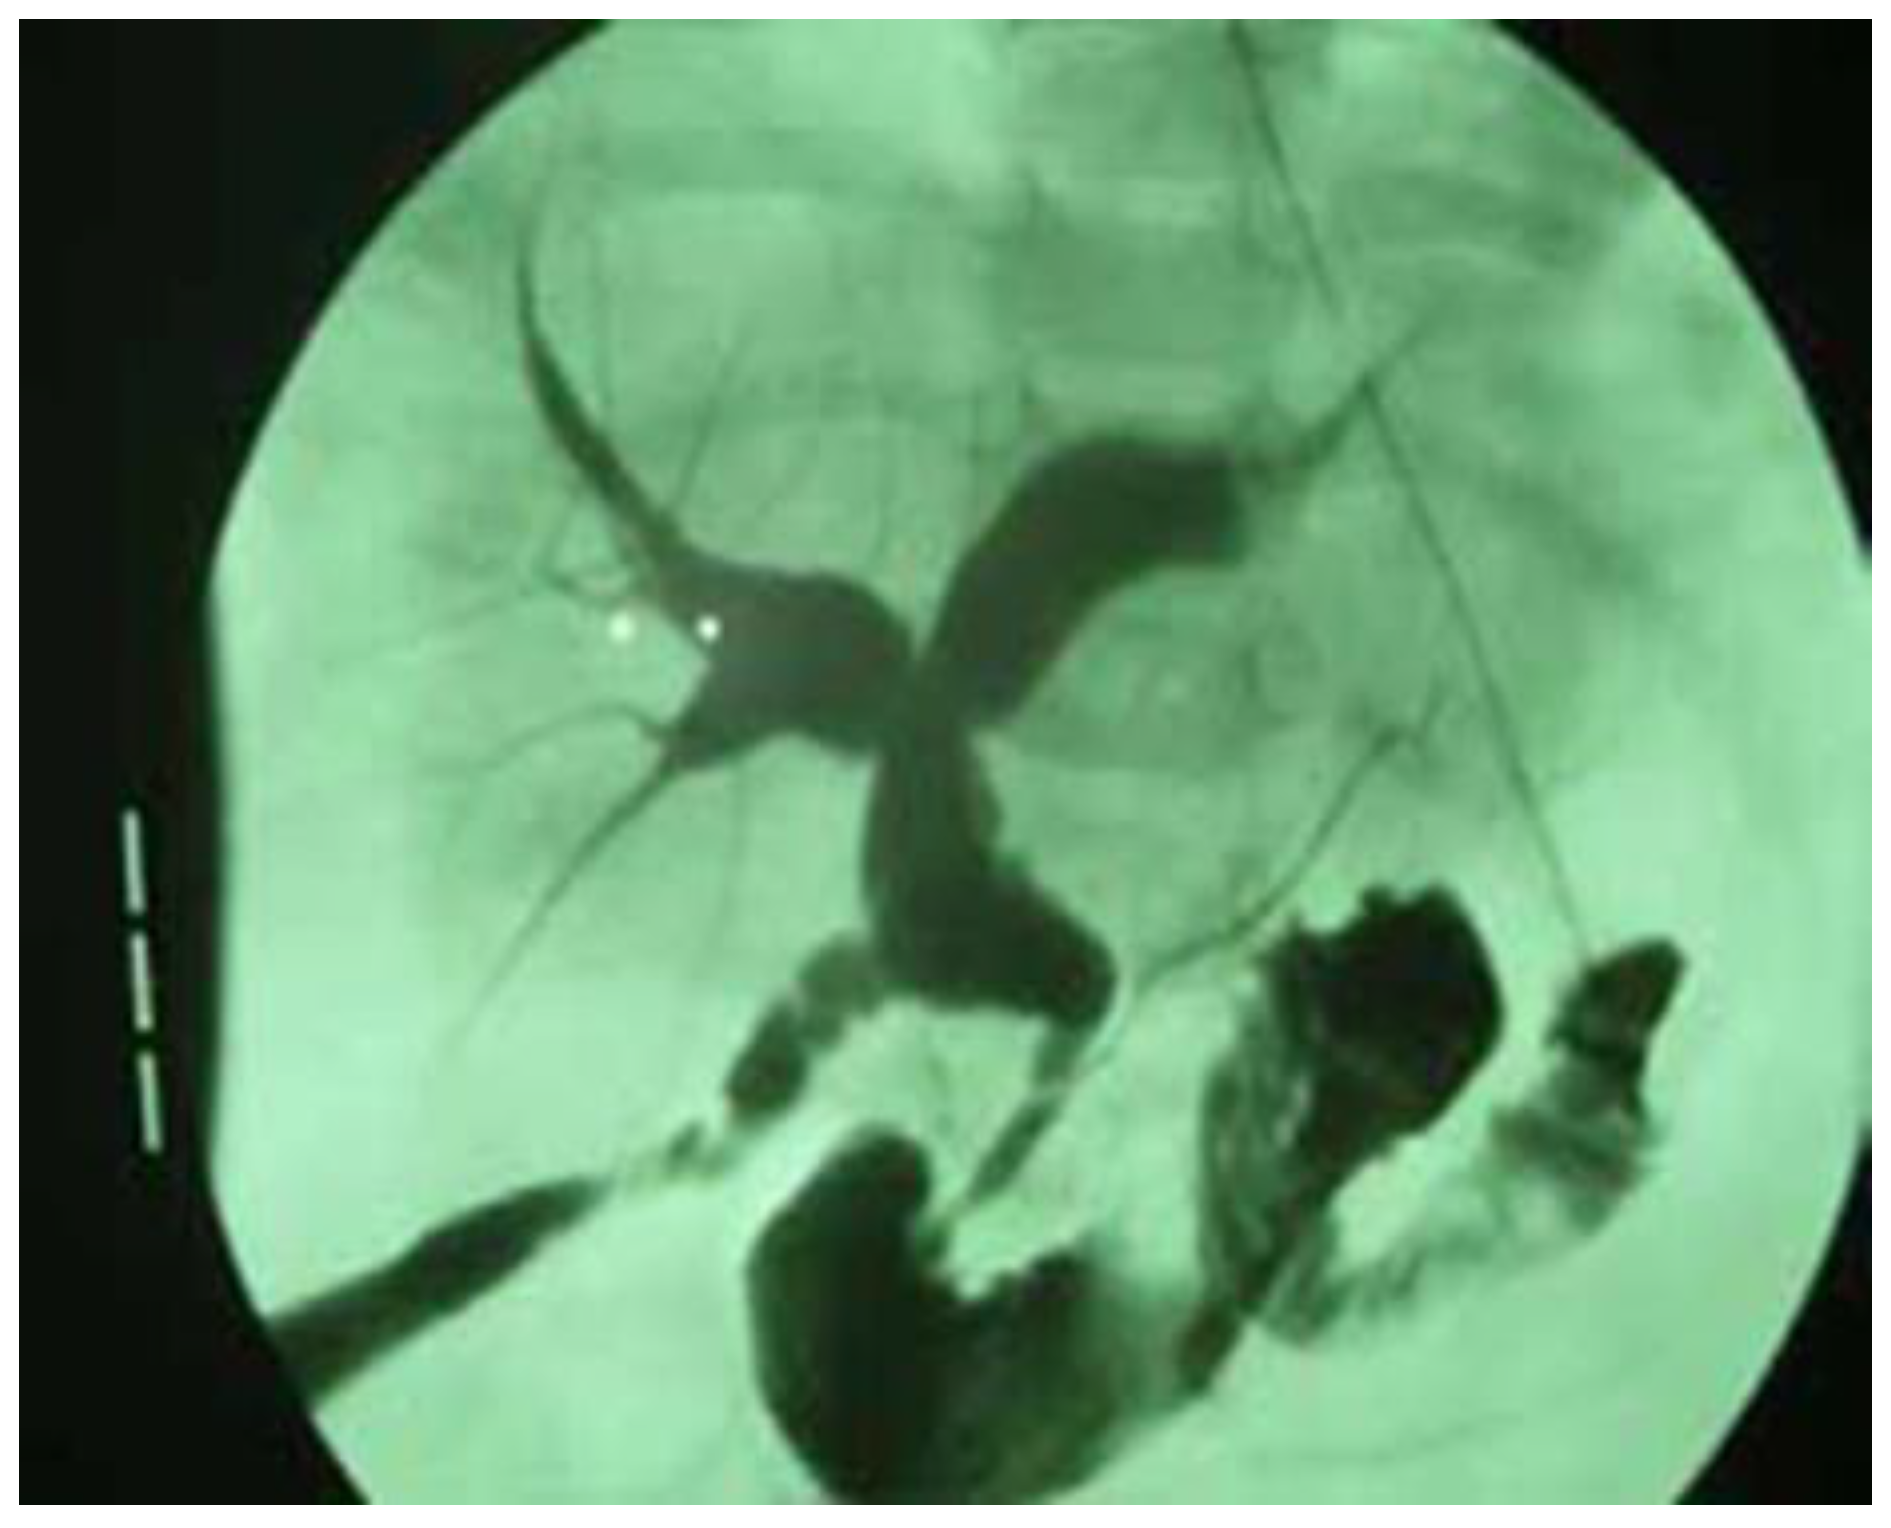

Finally, prior to the surgical correction of the anomaly, an intraoperative cholangiography was performed in all patients to confirm the diagnosis (Figure 3).

Figure 3. Intraoperative cholangiography in a 21-month-old boy, showing a dilated CBD with a diameter of 9 mm and an anomalous pancreaticobiliary junction.